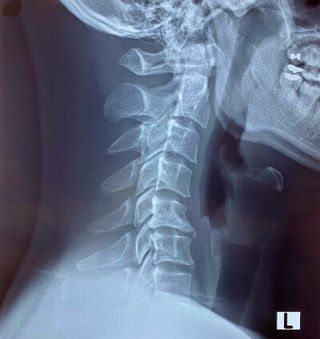

I consulted a doctor and he asked me to get x-ray of cervical spine. The x-ray stated loss of normal cervical lordosis so cervical strain and no cervical rib. The doctor has prescribed some medicine and advised for physiotherapy.

Cervical lordosis is lost. In general this is represented by a magnetic resonance imaging MRI scan. Frequently such studies reveal no other significant findings apart from a loss of cervical lordosis either under the form of a simple straightening of the spine or even an inversion of the normal curvature into a kyphosis. When there is a loss of cervical lordosis this means the cervical spine in the neck has lost its healthy c-shaped curvature and becomes straighter or the curve can be reversed known as a reverse curve.

Lordosis describes the normal front-to-back curvature of multiple areas of the spine including the neck. Loss of cervical lordosis can result in straightening of cervical spine or in severe cases it can reverse the curve. The condition is also called cervical kyphosis.

Frequently such studies reveal no other significant findings apart from a loss of cervical lordosis either under the form of a simple straightening of the spine or even an inversion of the normal curvature into a kyphosis. Loss of cervical lordosis is a diagnostic finding most often seen on MRI reports in association with chronic neck pain. Reduced curvatures in the neck are called hypolordotic conditions.